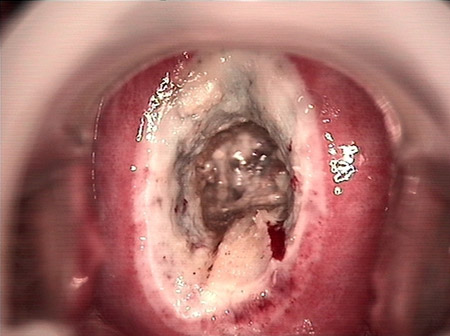

婦科leep錐切手術(shù) CIN2-3

• CIN 2-3 碘著色后CIN 2-3 碘著色后